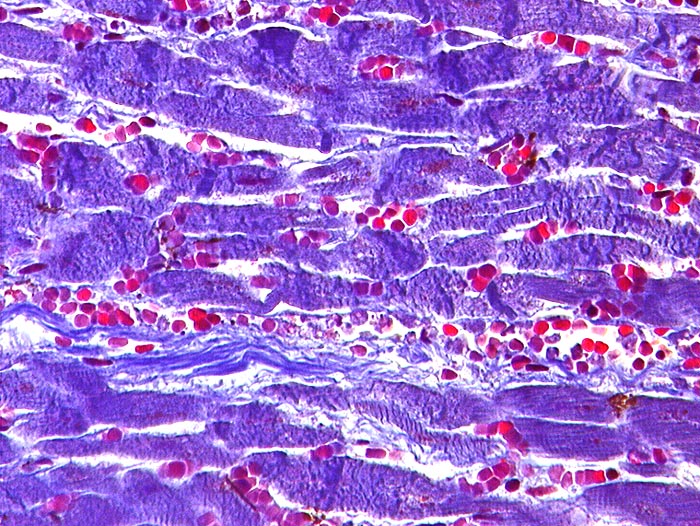

PathoPic ID 202 - Perakuter Myokardinfarkt

Perakuter Myokardinfarkt

vaskulär / Durchblutungsstörung

Herz links

Kardiovaskuläres System

Nekrotische Myokardfasern mit zahlreichen Kontraktionsbändern. Ein granulozytäres Entzündungsinfiltrat fehlt.

St.n. vierfachem Aortokoronarem Bypass vor 10 Jahren.

Histologie